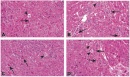

Некротични клетки показват увеличена еозинофилия, която се дължи отчасти на загуба на нормалната базофилия предавана от РНК в цитоплазмата и отчасти на повишено свързване на интрацитоплазмен еозин за денатурирани протеини. Некротичната клетката може да има стъклообразен вид, за разлика от нормалните клетки, главно в резултат на загубата на гликогенни частици.

При електронна микроскопия на некротични клетки се наблюдават явни прекъсвания в плазмените мембрани и органели, маркирана дилатация на митохондриите с появата на големи аморфни плътности, интрацитоплазмени отломки и агрегати, вероятно представляващи денатуриран протеин.

Областите на некроза се характеризират чрез инфилтрация на възпалителни клетки. Макрофагите и неутрофилите навлизат в областта на некроза в продължение на няколко дни и седмици, за да се фагоцитират мъртвите клетки и свързаните с тях клетъчни остатъци. Такива големи площи от загубата на клетки и възпаление често се виждат лесно в патологични образци, дори и без микроскопско изследване.